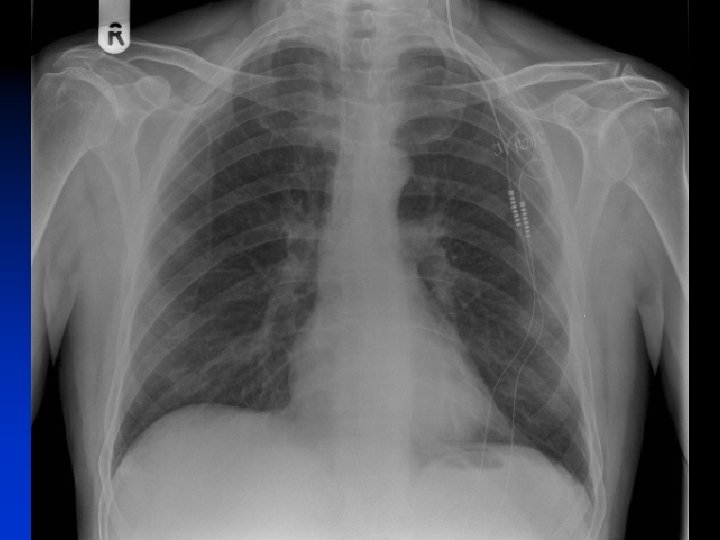

First Meeting n n n Check have been fully assessed in Headache Neurology Clinic (chronic, disabling, intractable) General fitness & airway satisfactory; reflux? MRI ? (because can’t have MRI once ONS is implanted) Any major surgery planned ? (because restriction of monopolar diathermy once ONS implanted) Explaining procedure

Stages of the operation n Insertion of electrodes « LA n + Sedation Test stimulation of electrodes « Awake n Insertion of battery and tunnelling of leads « Asleep n n (GA with LMA) Alternatively GA throughout if difficult airway or reflux USA: 2 stage procedure

2 -3 days later n n n n Activate implant Set initial parameters Pleasant radiating occipital paraesthesiae bilaterally Patient education to use handset for continuous comfortable stimulation Patient given implant ID card Advised to restrict strenuous activity in first 8 weeks Drive when comfortable, but switch implant off while driving Restrictions after 2 months: no MRI, scuba diving below 10 m